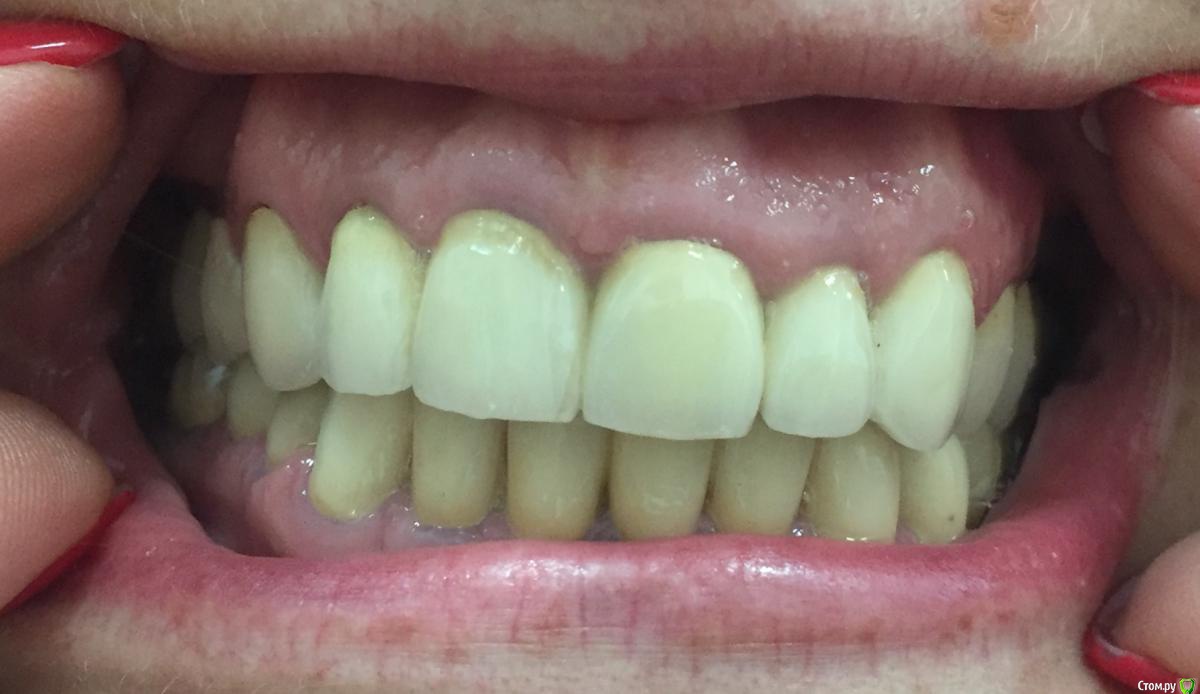

Ирина 0372 Опубликовано 4 февраля, 2019 Поделиться Опубликовано 4 февраля, 2019 Здравствуйте! Прошу совета, так как прошерстила просторы инет, не нахожу ответа...В 2011 году поставила металлокерамические коронки на все зубы. Ходила в клинику целый год, отдала 413 тысяч, сделали. Вроде все ничего, по сравнению с тем, что было...правда потом уже обнаружила, что как-то не симметрично стоят передние зубы, правая сторона чуть ниже, чем левая, на жевательных, у десны, видно железо, на некоторых зубах... Удивило и то, что по всему рту стоят мосты: один мост на пять зубов. Конечно привыкала долго, изменилась дикция, так как межзубное пространство отсутствует.. На вопрос почему мосты на передних зубах, не лучше ли сделать каждый отдельно, врач ответил:" Нельзя, так надежнее"Сейчас появилась возможность заменить передние металлокерамические коронки, на диоксид циркония.Очень хочется поставить на каждый зуб отдельную коронку!!! Хочется вернуть мою прежнюю дикцию (сейчас у меня временами просвисты, буквы "Ц" и "С" произношу как-то не так, как с живыми зубами. Хочется чтобы все стояло ровно, а не так, как сейчас: перекошенные напрочь зубы! Конечно в ту клинику, где ставила коронки больше никогда не пойду!Собственно вопрос заключается в следующем: допускается ли протезирование передних зубов отдельными коронками? Или обязательно должен стоять мост?Буду благодарна вашим ответам, дорогие врачи! Ссылка на комментарий

Ирина 0372 Опубликовано 4 февраля, 2019 Автор Поделиться Опубликовано 4 февраля, 2019 (изменено) ]Покажите панорамный снимокНашла снимок. Но, к сожалению, не свежий.. Это еще до постановки коронок. Могу сказать, что на верхней челюсти изменилось то, что зубы теперь не живые и все каналы хорошо запломбированы. А на нижней слева, внизу, появились три импланта. У меня есть КТ на диске из клиники, где ставила импланты, но почему то файлы не открываются, видимо нужна спец.программа... Изменено 4 февраля, 2019 пользователем Ирина 0372 Ссылка на комментарий

Ирина 0372 Опубликовано 7 февраля, 2019 Автор Поделиться Опубликовано 7 февраля, 2019 Покажите панорамный снимокВот, сегодня сделала: Ссылка на комментарий

DmitrySH Опубликовано 7 февраля, 2019 Поделиться Опубликовано 7 февраля, 2019 Здравствуйте, с лечением в целом все хорошо. Имплантацию справа почему решили не делать? Ссылка на комментарий

Ирина 0372 Опубликовано 7 февраля, 2019 Автор Поделиться Опубликовано 7 февраля, 2019 (изменено) Здравствуйте, с лечением в целом все хорошо. Имплантацию справа почему решили не делать?Спасибо Вам за ответ. Имплантирование вообще не планировала, но лет через пять после установки протезов, вспухла десна слева. После похода к доктору, выяснилось, что мне забыли поставить вкладку в тот зуб, возле которого появилась вздутие, из-за этого появилась киста. Пришлось удалить три зуба и поставить имплантанты. Скорее всего, со временем, придётся и справа ставить импланты.. Но наверно ещё можно так походить? Как Вы думаете, могу я заменить мост на пять зубов сверху, на отдельные коронки? Кроме желания, есть ещё и проблемка: на одном ( левом центральном зубе, я не знаю нумерацию по-правильному)), появилась трещина.. Кстати, как правильнее: импланты или имплантанты? Изменено 7 февраля, 2019 пользователем Ирина 0372 Ссылка на комментарий

Ирина 0372 Опубликовано 7 февраля, 2019 Автор Поделиться Опубликовано 7 февраля, 2019 (изменено) Если речь про трещину корня, то стоматология не умеет лечить трещины. Такие зубы подлежат удалению и имплантации. соответственно коронки снимаются, делается временное протезирование, проблемный зуб удаляется, ставится имплант и потом коронки по отдельности.Если речь про трещину корня, то стоматология не умеет лечить трещины. Такие зубы подлежат удалению и имплантации. соответственно коронки снимаются, делается временное протезирование, проблемный зуб удаляется, ставится имплант и потом коронки по отдельности. Нет, речь о трещине на самой коронке. Вы же не увидели трещин на каком-нибудь корне на снимке.. Речь о том, что хочу поменять мост на передних верхних зубах на отдельные коронки из диоксида циркония. Вы ответили, что в целом всё в порядке, но не сказали возможно ли заменить мост? В моем случае это возможно? Изменено 7 февраля, 2019 пользователем Ирина 0372 Ссылка на комментарий

___49___ Опубликовано 7 февраля, 2019 Поделиться Опубликовано 7 февраля, 2019 (изменено) В моем случае это возможно? исходя из предоставленной Вами информации , установить отдельные коронки на верхних 4 резца технически возможно. Но есть прикус которого я не вижу (и еще пару моментов) требующие очной консультации , для более достоверного ответа . Изменено 7 февраля, 2019 пользователем ___49___ 2 Ссылка на комментарий

DmitrySH Опубликовано 7 февраля, 2019 Поделиться Опубликовано 7 февраля, 2019 Нет, речь о трещине на самой коронке. это не страшно. Подумал что вы про корень зуба. В моем случае это возможно? Да, возможно. Но как правильно подметил коллега, есть нюансы которые надо оценивать очно 2 Ссылка на комментарий